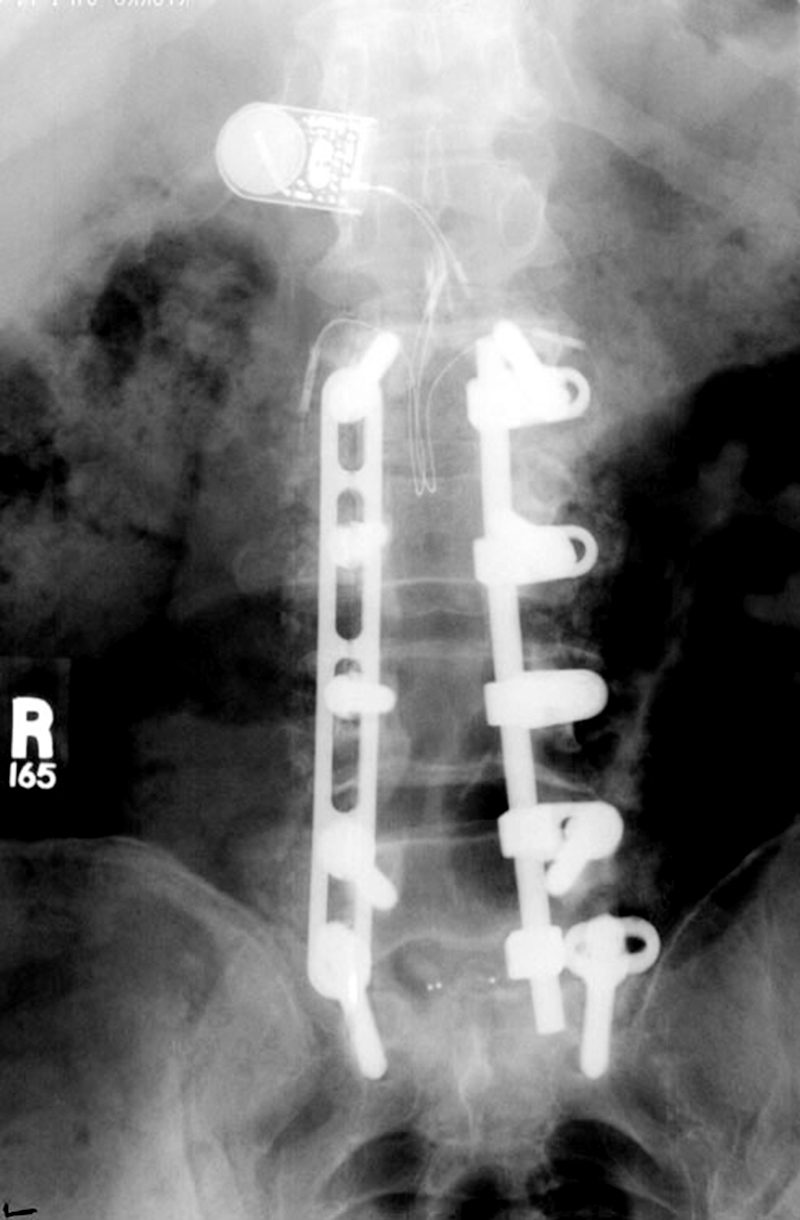

| Harrington rods |

Harrington rods |

| The hooks on these rods are designed for distraction. From Hunter, 1994 |

Harrington rods are at the thorocolumbar junction stabilizing a vertebral body fracture. The hooks (thick arrows) anchor the rods in the lamina. Segmental wires around the lamina (thin arrow) supplement the fixation. From Hunter, 1994 |

Harrington rods (flanged ends) and Knodt rods (threaded rods) have hooks along the rods; designed to either distract the spine or compress it, depending on the direction in which the hooks are placed. |